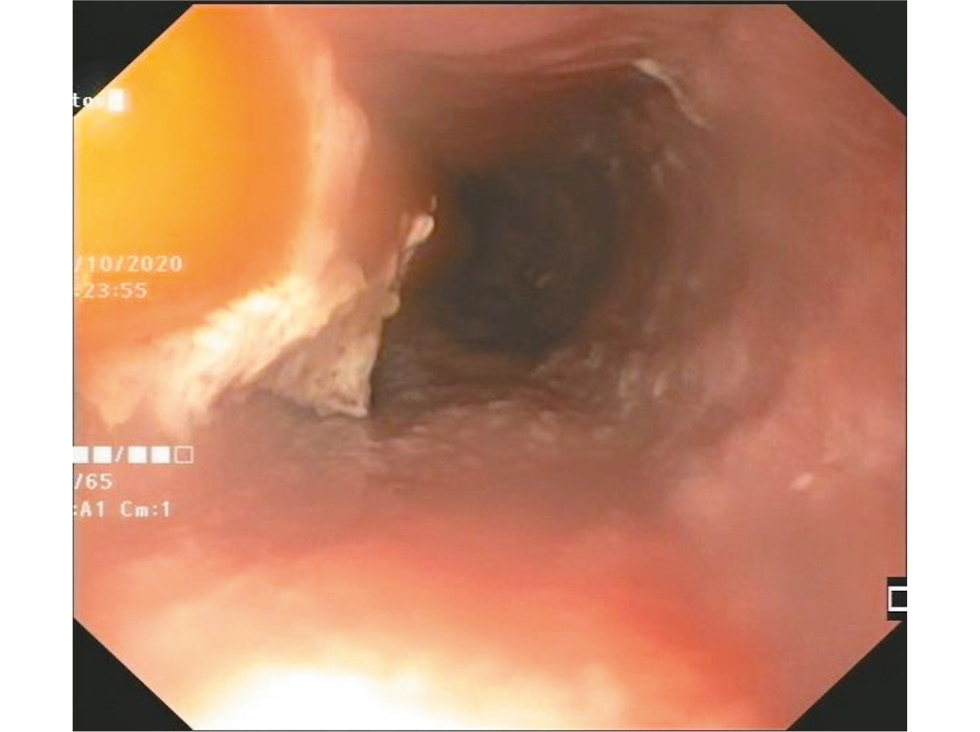

Методика ПОЭМ состояла из 3 этапов:

- Создание тоннеля в подслизистом слое пищевода. В подслизистый слой пищевода выполняли инъекцию 6% раствора гидроксиэтилкрахмала (6 детям) или гиалуроновой кислоты (2 детям), окрашенных индигокармином до светло-синего цвета. Затем на расстоянии 25–28 см от загубника и 13–15 см от пищеводно-желудочного перехода производили продольный разрез слизистой оболочки грудного отдела пищевода длиной от 1,5 до 2,5 см. Далее путём диссекции в режиме спрей-коагуляции создавали длинный тоннель в подслизистом слое, который своим дистальным слепым концом заканчивался на уровне субкардиального отдела желудка (рис. 3). В ходе диссекции через нож дополнительно вводили необходимое количество красящего раствора в подслизистый слой. Для обработки крупных сосудов или остановки кровотечения использовали мягкую диатермокоагуляцию.

Рис. 3. Пероральная эндоскопическая миотомия: создание подслизистого тоннеля.

Fig. 3. Peroral endoscopic myotomy: creating of submucosal tunnel.